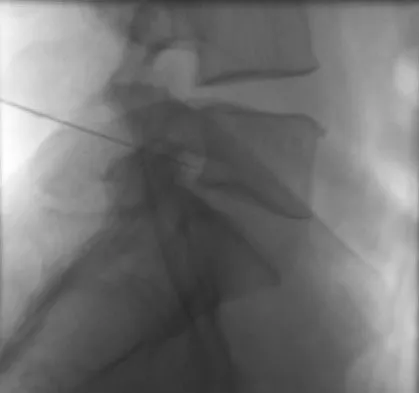

A 44-year-old woman has had lower extremity dysesthesias, urinary incontinence, and has been unable to walk for the past 2 days. She reports no pain or history of trauma. She notes that 3 weeks ago she missed work for 2 days because of back pain, but it resolved with rest. Examination shows decreased or absent sensation below the knees, no motor function below the knees, and decreased rectal tone. Catheterization results in a postvoid residual of 2,000 mL. Plain radiographs and MRI scans without contrast are shown in Figures 1a through 1d. What is the next most appropriate step in management?

Explanation

The patient has had a clear and sudden onset of a profound neurologic deficit. The radiographic studies suggest a lesion in the conus medullaris that appears to be intradural and intramedullary. MRI, with and without contrast, will best evaluate this mass further. The addition of gadolinium allows further evaluation of vascularity and the extent of the lesion. Eichler ME, Dacey RG: Intramedullary spinal cord tumors, in Bridwell KH, Dewald RL (eds): The Textbook of Spine Surgery, ed 2. Philadelphia, PA, Lippincott-Raven, 1997, vol 2, pp 2089-2116.